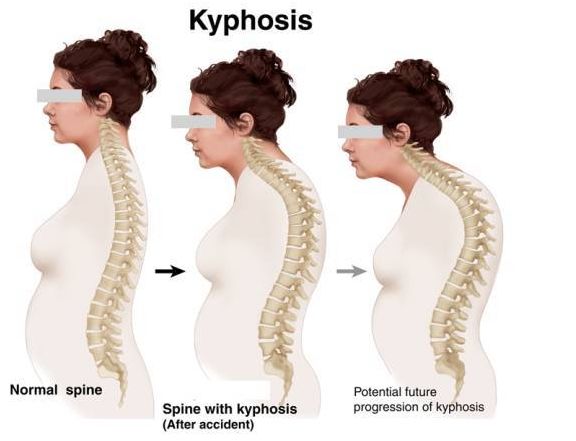

第二种,脊柱 后弯 驼背 + 骨盆前倾 + 脖子前探

女生特别常见,尤其是长期穿高跟鞋,喜欢撅屁股的小主们。看起来屁股翘,但是一般小肚子特别大, 驼背,而且腿打着圈的不直,膝盖特别容易出问题,别随意跑马拉松。

脊柱上的三个曲度都发生了变化,主要就是伏案和久坐很容易造成。

· 年龄 刚出生的小孩和成年人的脊柱 状态 是不一样的,成年人和 老年人 的身体状态也是不一样的。当人的年龄超过 45 岁之后,骨骼会慢慢衰退,椎间盘 里面的水分和骨骼密度也随之降低,这些都会造成 人体 的变化,最常见的就是驼背。

· 驼背:由于胸椎过度向后 弯曲 导致,从侧面观察时可以看到上背部向后拱起。驼背和圆肩有时容易搞混,要明确是胸椎向后拱还是肩膀向内收。